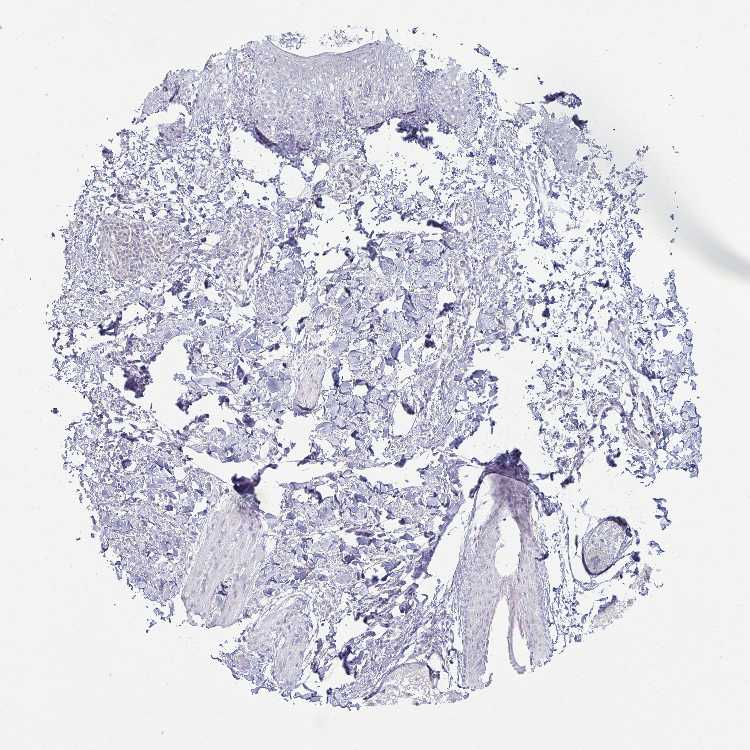

SKIN 1 - Antibody stainingi

Antibody staining in the annotated cell types in the current human tissue is reported as not detected, low, medium, or high, based on conventional immunohistochemistry profiling in selected tissues. This score is based on the combination of the staining intensity and fraction of stained cells.

Each image is clickable and will lead to virtual microscopy that enables deeper exploration of all samples and also displays staining intensity scores, fraction scores and subcellular localization as well as patient and tissue information for each sample.

Antibody HPA034996Antibody HPA034997Antibody CAB004648

Langerhans Not detectedNot detectedNot detected

Fibroblasts Not detectedNot detectedMedium

Keratinocytes Not detectedNot detectedLow

Melanocytes Not detectedNot detectedNot detected

SKIN 2 - Antibody stainingi

Epidermal cells Not detectedNot detectedLow